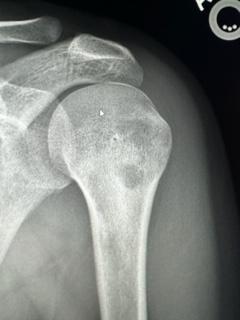

IMG_3783